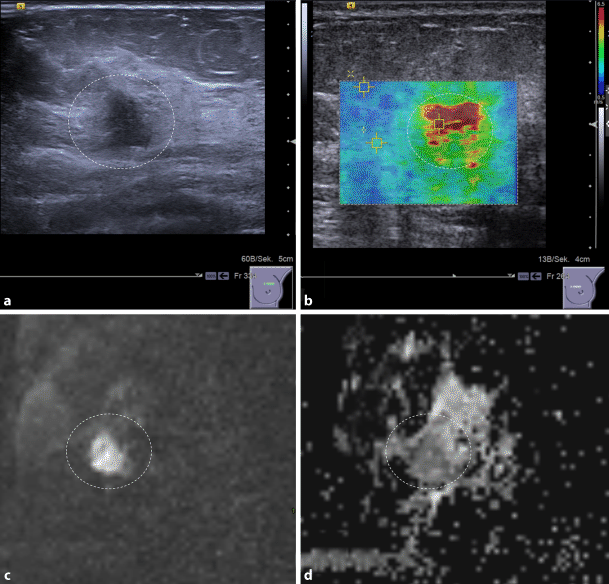

As a potential imaging biomarker, an interesting application of ARFI may be in “ruling in” or “ruling out” malignancy (Fig. 1). Initial data show that it is feasible to downgrade suspicious breast lesions according to B‑mode features without missing any invasive cancers or intermediate-to-high-grade in situ carcinomas if they are associated with a very low SWV. Thus, unnecessary breast biopsies may be avoided in up to 15% of cases [25]. On the other hand, a lesion demonstrating a very high SWV is highly likely to be malignant, irrespective of its B‑mode features and re-biopsy may be indicated in the case of a benign histological result.

Diffusion-weighted imaging (DWI) is an MRI technique that does not require intravenous contrast medium injection. DWI measures water diffusion and thus allows conclusions to be drawn about tissue microstructure [32] (Fig. 1). The microstructural changes that influence water diffusion in neoplastic breast tissue are still poorly understood: In general, neoplastic tissues are characterized by changes in cellularity, proteolytic activity, and reactive desmoplastic induration leading to restricted extracellular water diffusion. DWI sequences qualitatively assess the molecular diffusion, which presents as a high signal when water movements are restricted [32]. Diffusion can be quantified by calculating the apparent diffusion coefficient (ADC) from raw DWI images. High ADC values (>1.4 × 10−3 mm/s) correspond to high diffusivity, a finding that generally rules out malignancy. It has been shown that by using a high ADC threshold, unnecessary biopsies may be omitted in different clinical settings [33, 34]. In addition, quantitative ADC measurements used as an imaging biomarker allow invasive breast cancer to be distinguished from in situ breast cancer with a sensitivity of 78% and a specificity of 90% (with a threshold of 1.01 × 10 mm/s) [35]. Finally, quantitative ADC is a promising marker to assess response to neo-adjuvant treatment as it is sensitive to variations in tumor cellularity and necrosis that appear as an increase in ADC values before changes in lesion size and morphology [36].

Fig. 1

A 48-year-old woman with invasive ductal breast cancer, G3. The lesion (dashed circle) presents as an ill-defined hypoechogenic lesion on B‑mode ultrasound (a) that is associated with high SWV (4.6 m/s), coded red on the parametric ARFI overlay (b). The MRI-DWI scan of the same lesion shows a hyperintense lesion (c) corresponding to restricted diffusivity (1 * 10−3 mm2/s) that appears dark on the quantitative ADC map (d)